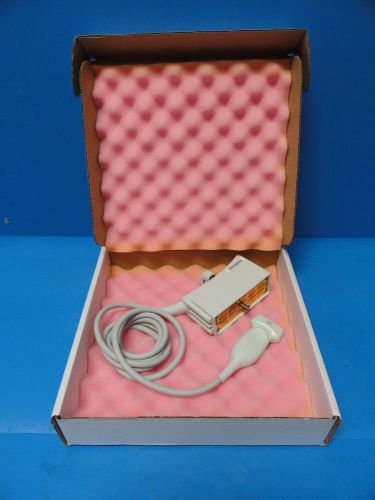

Siemens Acuson 8C4 Convex Probe W/ Pin-less Connector For Sequoia

Acuson 4V1 Vector Array Deep Tissue Abdominal Probe for Acuson Sequoia & Aspen

Siemens Acuson 5V2c Cardiac Ultrasound Transducer for Acuson Sequoia Series

SIEMENS ACUSON 13L5 Linear Array Ultrasound Transducer for Aspen series

2005 Acuson 6L3 P/N 08241112 Linear Array Ultrasound Probe for Acuson Sequoia

Siemens Acuson 15L8W Linear Array Ultrasound Probe for Acuson SEQUOIA series

Acuson 8C4 Pinless Ultrasound Probe

Acuson 8V3 Pinless Ulrasound Probe

Acuson 8V5 Pinless Ultrasound Probe

Acuson TE-V5Ms Pinless Ultrasound Probe

Acuson V5 with Pins Ultrasound Probe

Hitachi Aloka Model UST-574T-7.5MHz Linear Array Transducer Ultrasound Probe

ATL C5-2 40R Ergo Ultrasound Probe

ATL Curved Array C4-2 40R Ultrasound Probe

ATL Curved Array C8-5 14R Utlrasound Probe